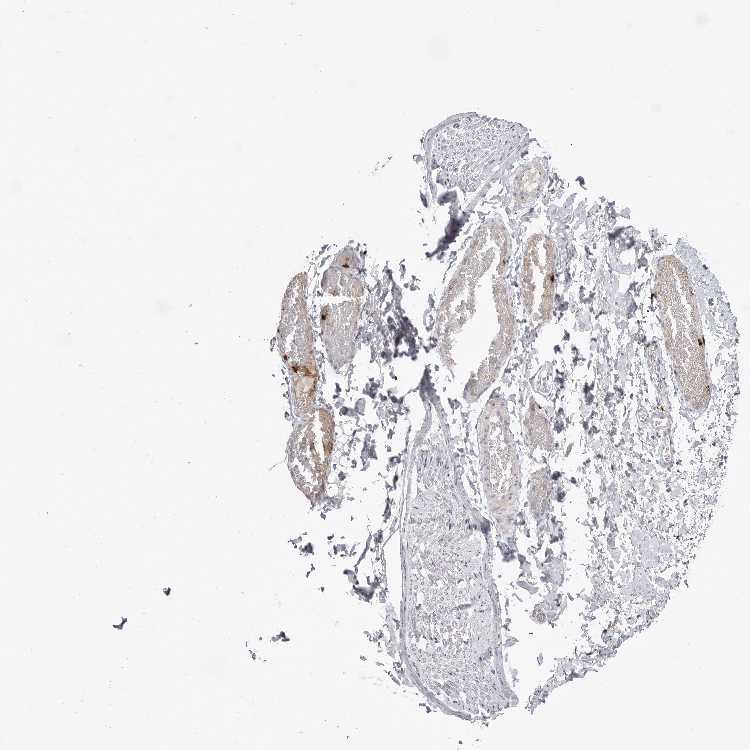

SOFT TISSUE 1 - Antibody stainingi

Antibody staining in the annotated cell types in the current human tissue is reported as not detected, low, medium, or high, based on conventional immunohistochemistry profiling in selected tissues. This score is based on the combination of the staining intensity and fraction of stained cells.

Each image is clickable and will lead to virtual microscopy that enables deeper exploration of all samples and also displays staining intensity scores, fraction scores and subcellular localization as well as patient and tissue information for each sample.

Antibody HPA027028

Fibroblasts Not detected

Peripheral nerve Not detected

SOFT TISSUE 2 - Antibody stainingi